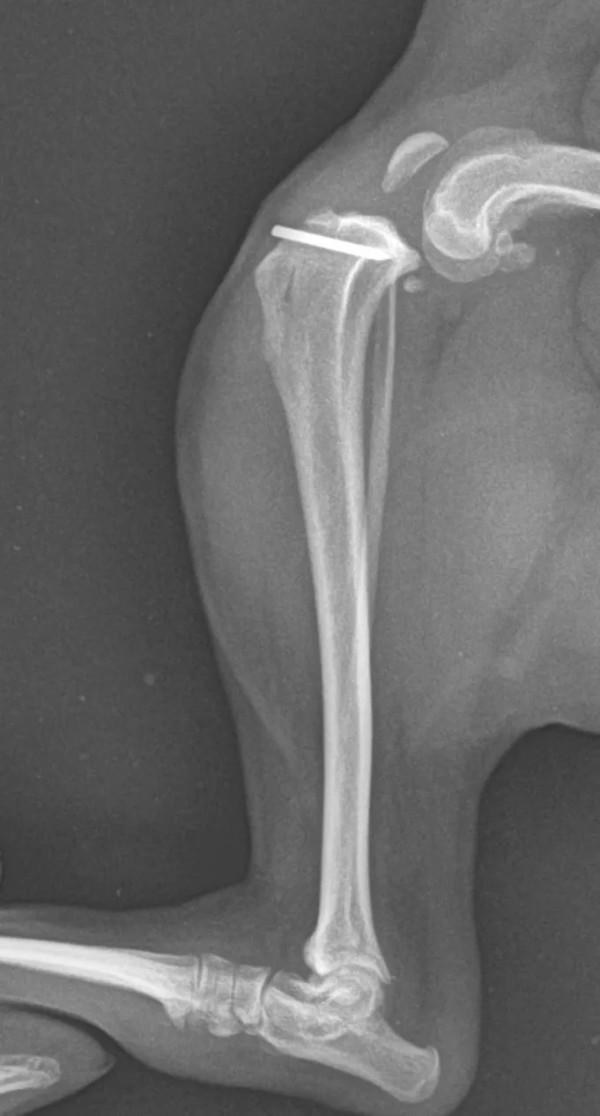

术中照片